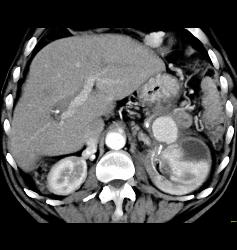

Page Kidney With Bleeding Splenic Artery Aneurysm- See Sequence